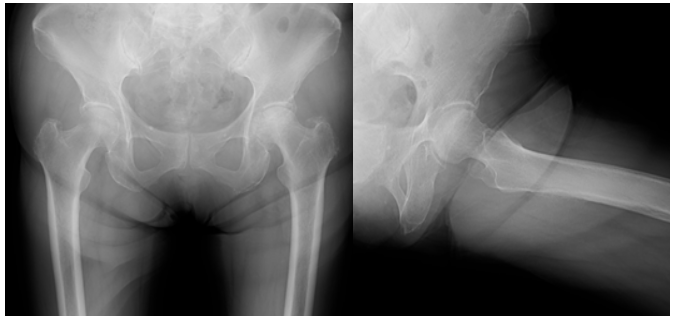

An 80-year-old woman with terminal lung adenocarcinoma developed left hip pain in February of year X-1. At her initial visit to our clinic in May, radiographs showed collapse of the left femoral head (Fig. 1). Magnetic resonance imaging (MRI) scans revealed a SIF (Fig. 2).

Figure 1: Radiograph at the first visit showing a subchondral fracture line in the left femoral head.

Figure 2: Magnetic resonance imaging at the initial visit. The T1-weighted image (left) shows a low-signal area in the femoral head, and the short tau inversion recovery image (right) shows a corresponding high-signal area, indicating a subchondral insufficiency fracture (arrowheads).